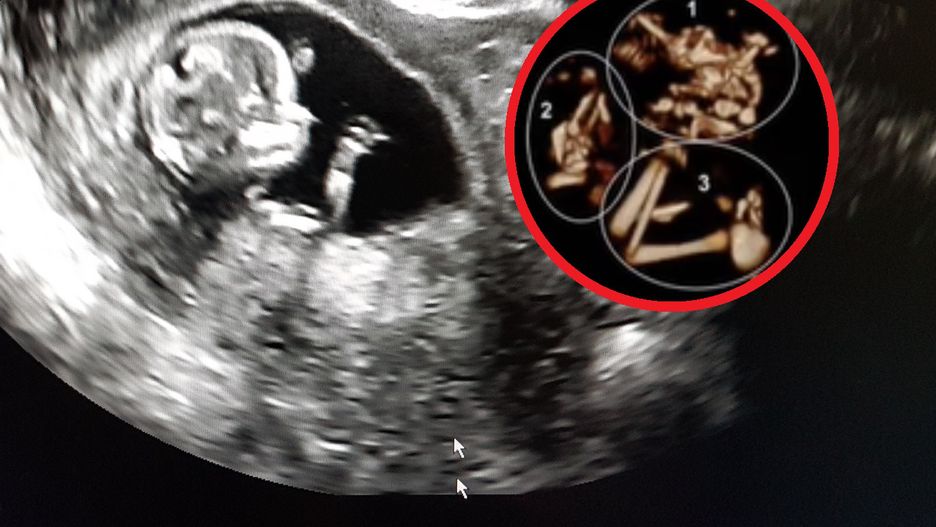

Badanie USG wykazało zmiany w czaszce płodu

Badanie USG jest wykonywane kilkakrotnie podczas trwania każdej ciąży. Dzięki niemu lekarz jest w stanie kontrolować, czy płód rozwija się prawidłowo i wyłapać na wczesnym etapie groźne zmiany. Podobnie było w tym przypadku. Przyszła mama była w 31. tygodniu ciąży. Podczas wykonywania kontrolnych badań odkryto groźne zmiany w czaszce dziecka, które potencjalnie wiązały się z ryzykiem obumarcia płodu.

Lekarz wykonujący ultrasonografię zauważył, że główka dziecka jest wyraźnie powiększona. Szczegółowa analiza wykazała, że w jego czaszce znajdują się kości drugiego płodu. Jak wyjaśniał medyk to tzw. "syndrom znikającego bliźniaka" - VTS (Vanishing Twin Syndrom).

W nagraniu opublikowanym w mediach społecznościowych ekspert szczegółowo wyjaśnia, na czym polega to zjawisko i z jakim ryzykiem się wiąże. Na zdjęciu USG widać wyraźnie ślady kończyn drugiego płodu w główce dziecka. Obumarły płód podlega naturalnemu wchłonięciu przez organizm matki lub drugi płód. Komplikacje pojawiają się, gdy proces zachodzi w późniejszych etapach ciąży, wtedy może to zagrażać życiu drugiego dziecka, może dojść też do krwawienia wewnątrzmacicznego.